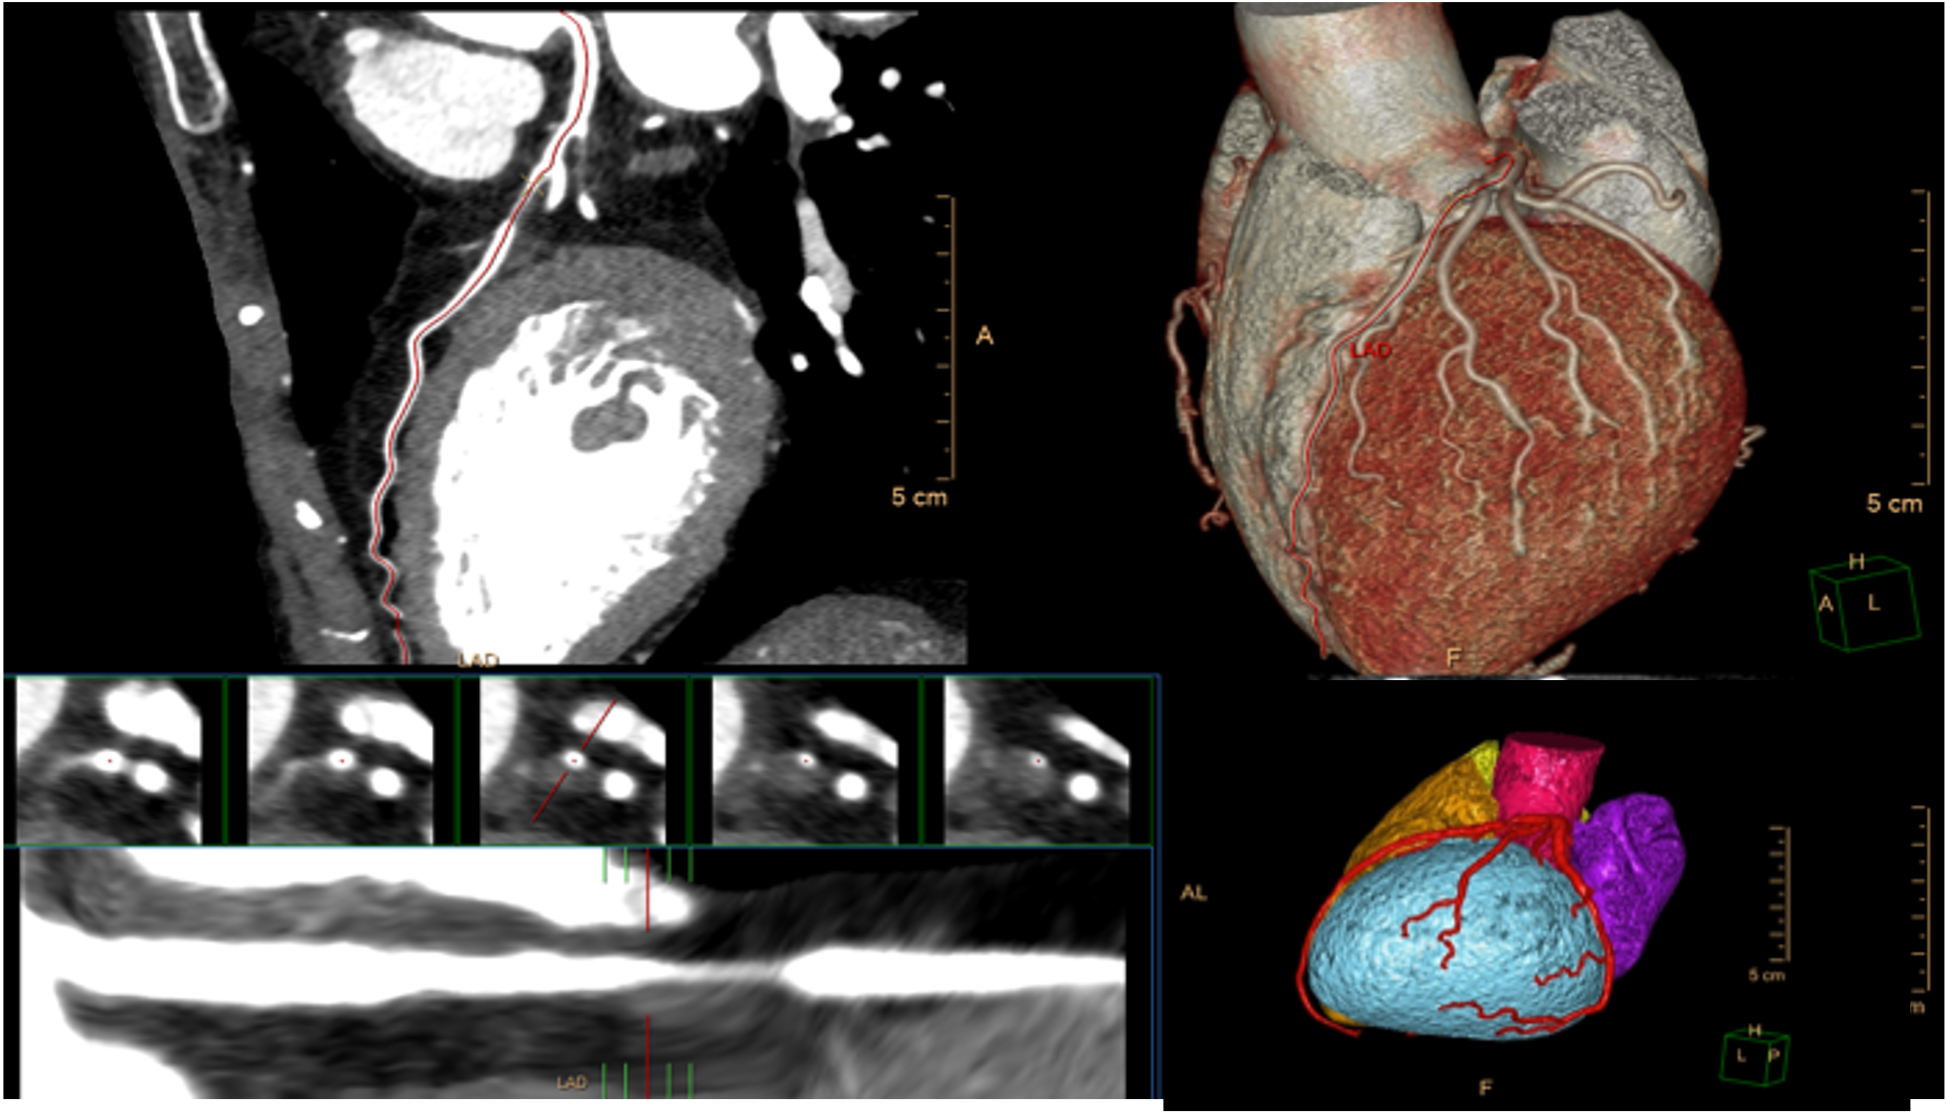

At RSNA, Philips will introduce its next-generation Advanced Visualization Workspace platform with AI-enabled algorithms and workflows. This latest innovation is vendor-neutral, providing a single, advanced platform for multiple modalities across cardiology, oncology, neurology, and radiology with a comprehensive suite of advanced visualization solutions to support care teams, and tailored to fit the needs of any hospital network, from a single workstation to an enterprise solution.

Philips Advanced Visualization Workspace now includes more than 70 clinical applications for clinical insights, designed to support workflow and diagnostic confidence as well as automated processing for multiple clinical domains across the continuum of care. New applications include the MR cardiac suite, an all-in-one environment for cardiac MR, providing one overview for all imaging data types to support diagnosis and report creation.